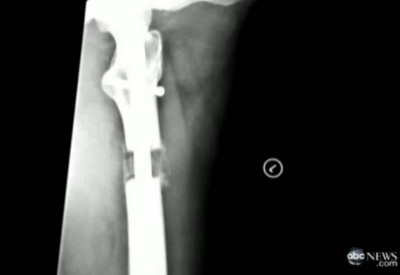

Y sĩ cưa đôi cẳng chân rồi nối vào giữa bằng một ống kéo ra kéo vô được, gọi là telescopic rod, sau đó ống được kéo giãn ra từ từ, mỗi ngày chừng 1 milimét. Tiến trình này hết sức tốn kém, khoảng $85,000, thời gian kéo dài ít nhất ba tháng, và đòi hỏi phải qua giai đoạn điều trị thể chất cực kỳ đau đớn. (TP)